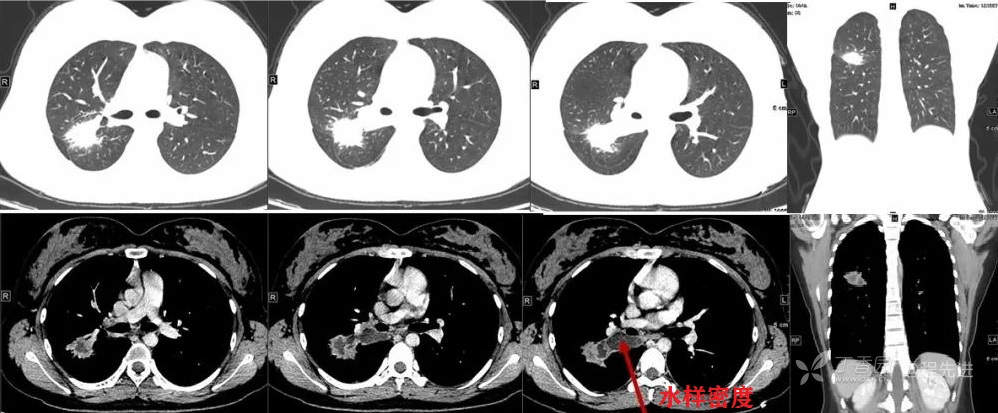

又3个月后,患者停药后复查,右上肺结节较前明显增大。现为进一步诊治,遂于今日来我院就诊。

CT 平扫CT值约40HU 增强CT值约80HU

1年后术前复查